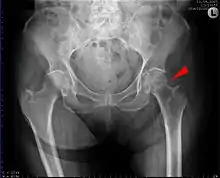

| Intertrochanteric hip fracture in a 17-year-old male | |

X-rays of the affected hip usually make the diagnosis obvious; AP (anteroposterior) and lateral views should be obtained.